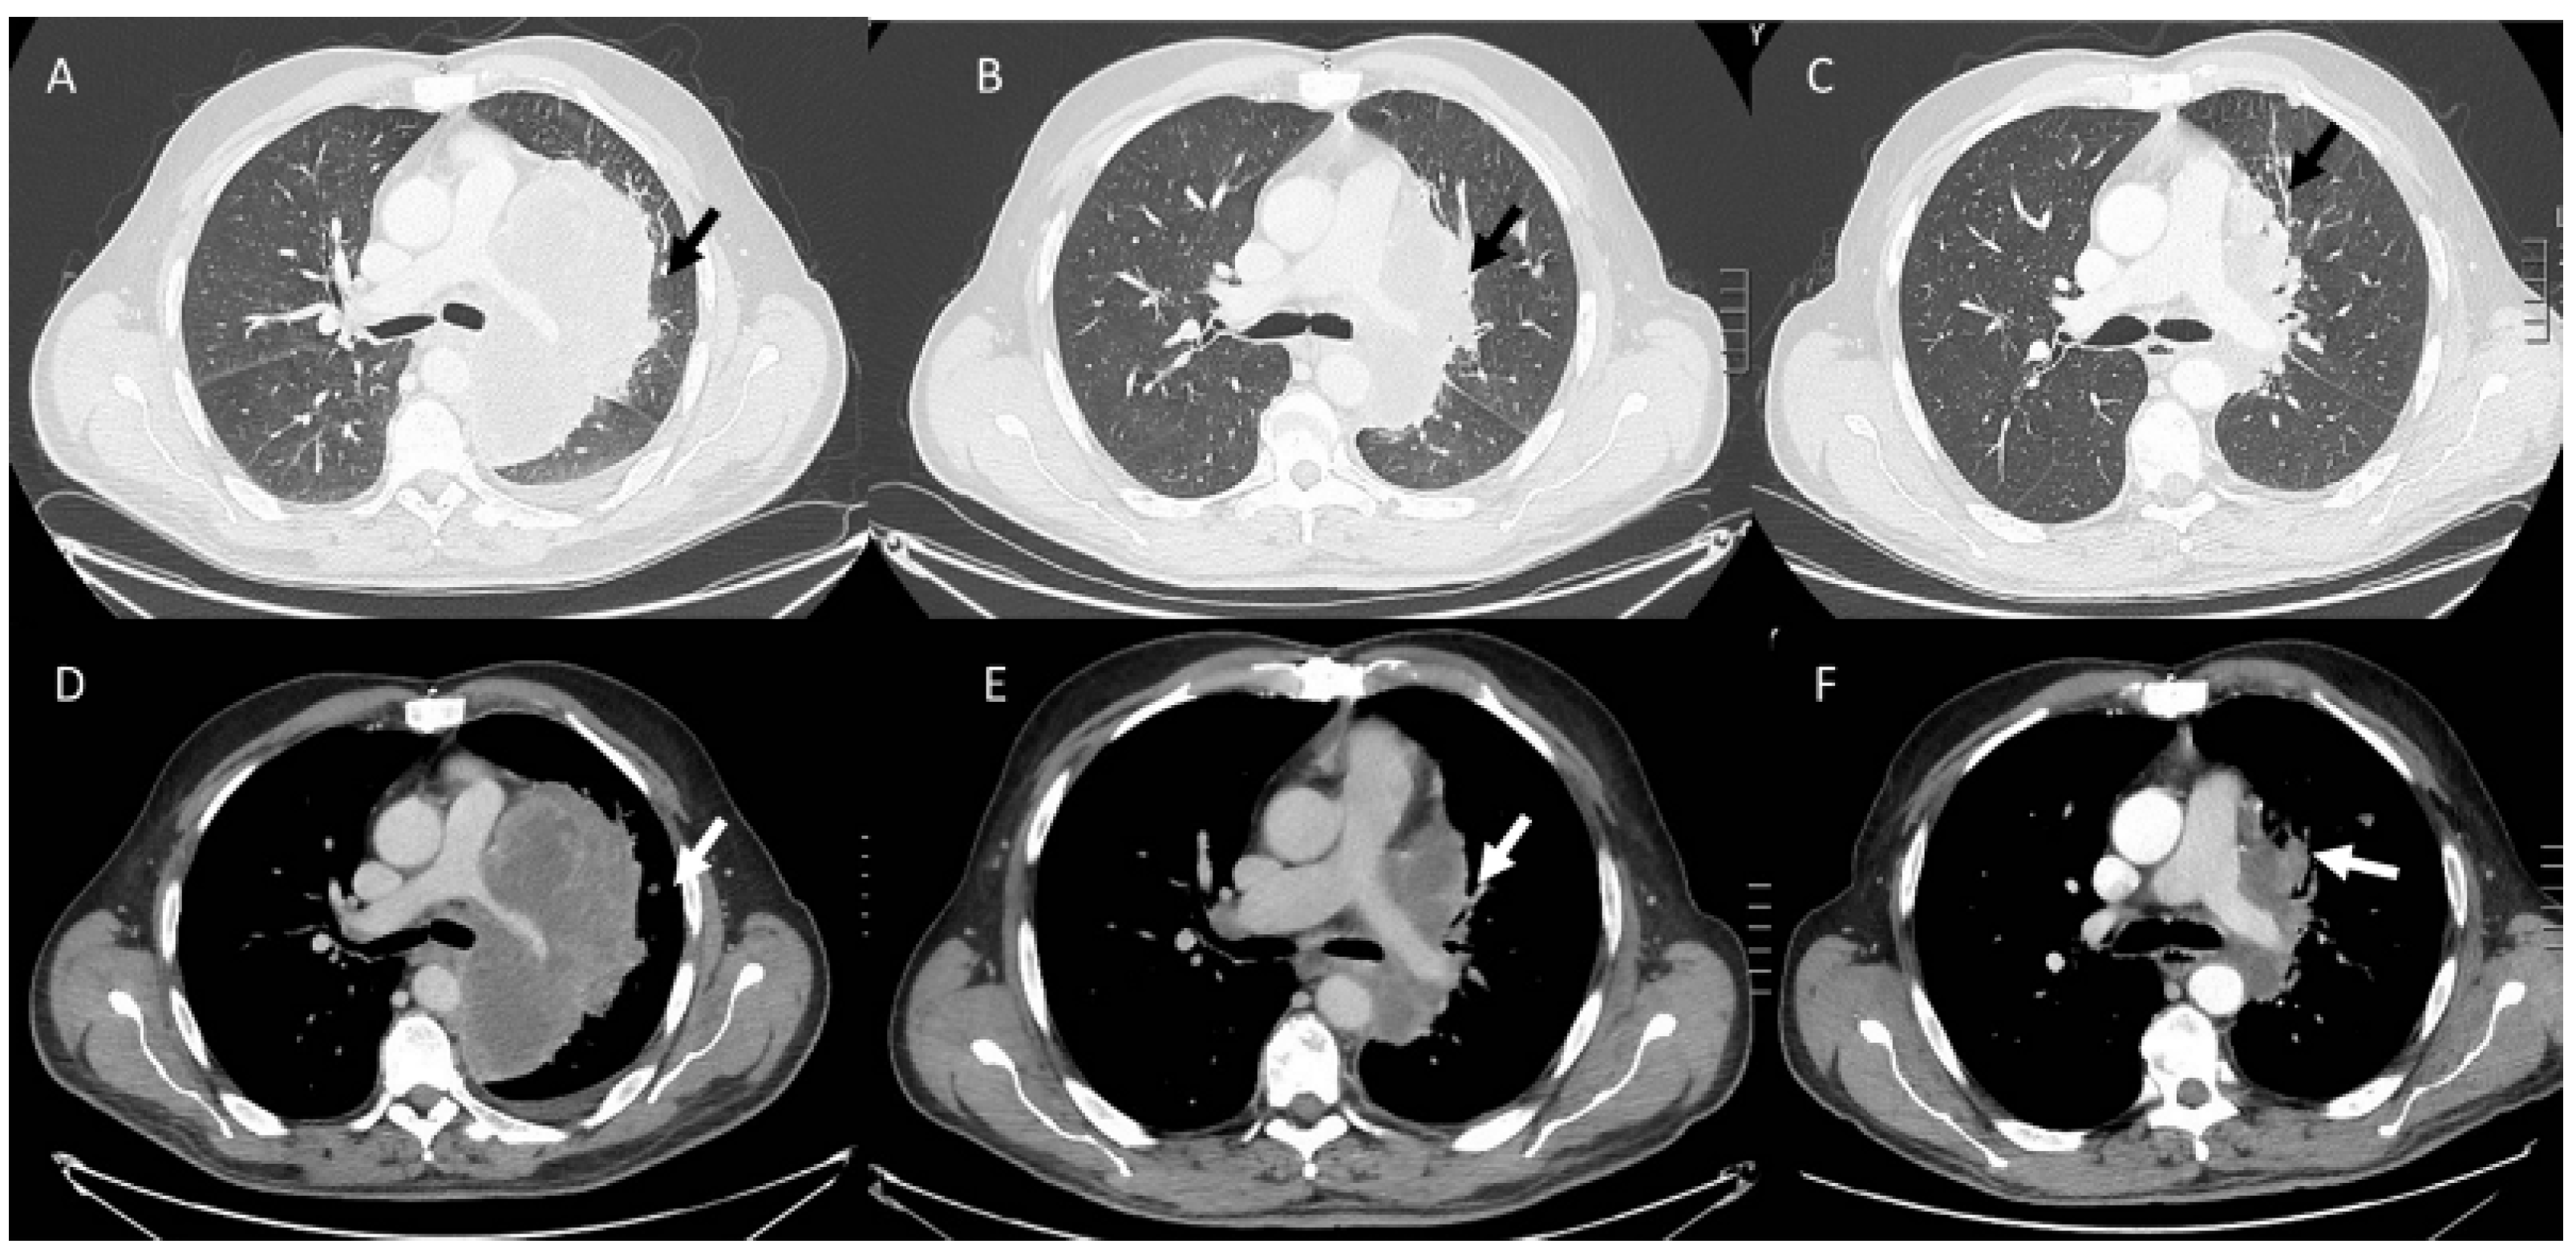

- Kalisz, K.R.; Ramaiya, N.H.; Laukamp, K.R.; Gupta, A. Immune Checkpoint Inhibitor Therapy-related Pneumonitis: Patterns and Management. Radiographics 2019, 39, 1923–1937. [Google Scholar] [CrossRef] [PubMed]

- Kwak, J.J.; Tirumani, S.H.; Van den Abbeele, A.D.; Koo, P.J.; Jacene, H.A. Cancer immunotherapy: Imaging assessment of novel treatment response patterns and immune-related adverse events. Radiographics 2015, 35, 424–437. [Google Scholar] [CrossRef]

- Tirumani, S.H.; Ramaiya, N.H.; Keraliya, A.; Bailey, N.D.; Ott, P.A.; Hodi, F.S.; Nishino, M. Radiographic profiling of immune-related adverse events in advanced melanoma patients treated with ipilimumab. Cancer Immunol. Res. 2015, 3, 1185–1192. [Google Scholar] [CrossRef]